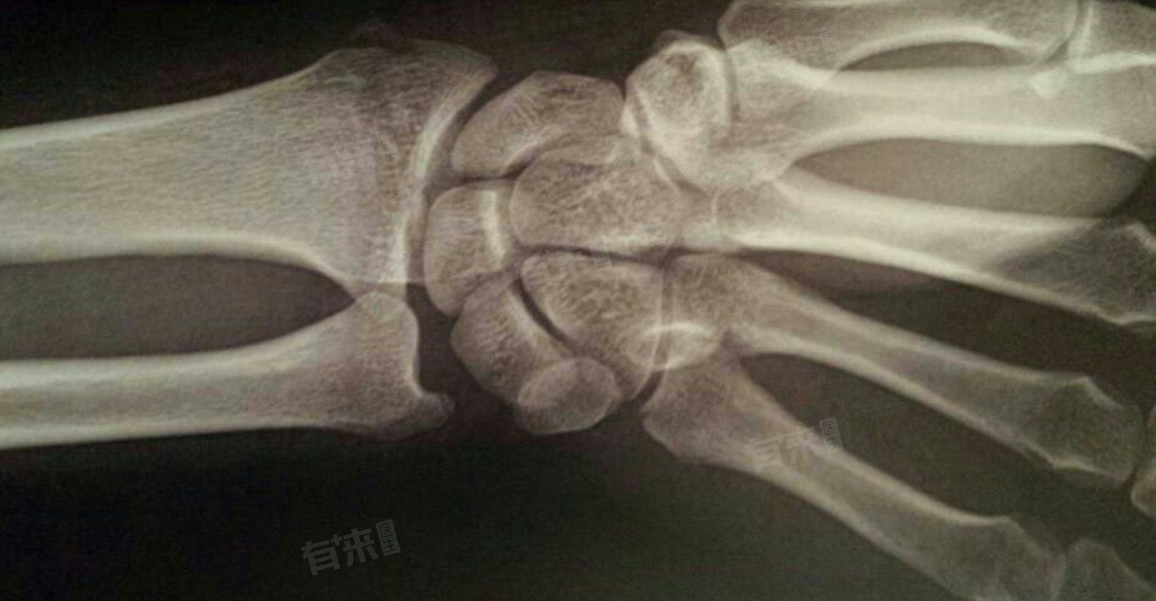

手腕脱臼后的恢复时间因多种因素而异,通常情况下,简单的手腕脱臼可能在1到2周内初步恢复,而较为复杂的脱臼则可能需要3到6周甚至数月才能完全康复。

- 手腕脱臼的严重程度是决定恢复时长的关键因素,简单脱臼即关节面仅发生轻微移位,周围的韧带、肌肉等软组织损伤较小时,复位后身体的修复机制能够相对迅速地发挥作用。

- 当手腕脱臼伴有较为严重的软组织损伤,如韧带撕裂或断裂时,恢复过程就会变得复杂且漫长。这类情况下不仅关节需要复位,受损的软组织也需要时间来修复。断裂的韧带愈合通常需要数周时间,期间关节需要保持固定,以促进韧带的愈合。